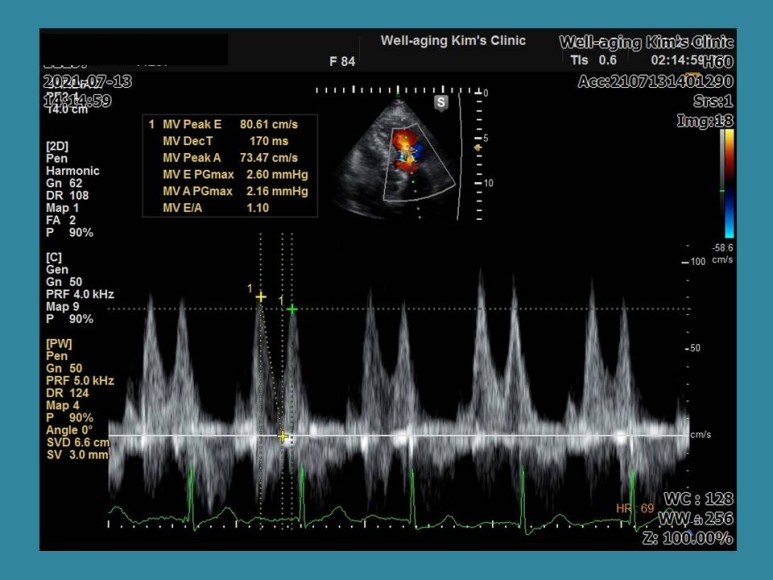

상행 대동맥에 흰 선이 움직이는 것이 대동맥이 박리된 상태.다음 증례는 83세 여성 환자로 성형외과 수술을 앞두고 수술 전 심장 평가를 위해 내원한 경우다.그쪽 병원에서 보내준 심전도는 정상이었지만.

심장 초음파 검사를 실시하는 동일 안심 장박동수가 130회/분으로 갑자기 빨라지고 다시 정상 리듬으로 돌아왔다.가

이번에는 갑자기 심장박동기가 40~50회/분으로 느려지다가 중간에 동성정지 소견이 나타나고 불규칙한 맥박으로 바뀌는 상황이 3~4회 반복됐다.

이 경우 전형적인 빈맥-서맥증후군에 해당하며 환자가 증상은 없었지만 일단 수술을 중단하고 상급병원으로서 24시간 심전도 등의 검사가 필요하다는 것을 설명하고 이 환자는 인공심장박동기를 삽입할 수도 있는 경우이다.

이 환자의 경우도 외부 병원에서 찍은 심전도는 정상이었으나 심장 초음파 검사 중 우연히 부정맥이 발현돼 진단을 받은 경우다.